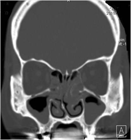

1. 嗅覚障害は発生部位から、気導性嗅覚障害、嗅神経性嗅覚障害、中枢性嗅覚障害に分類される。

1. 半数近くが鼻副鼻腔炎による気導性嗅覚障害である。

1. 好酸球性鼻副鼻腔炎に対する薬物療法として、局所噴霧ステロイド、経口ステロイド、生物学的製剤が有効である。